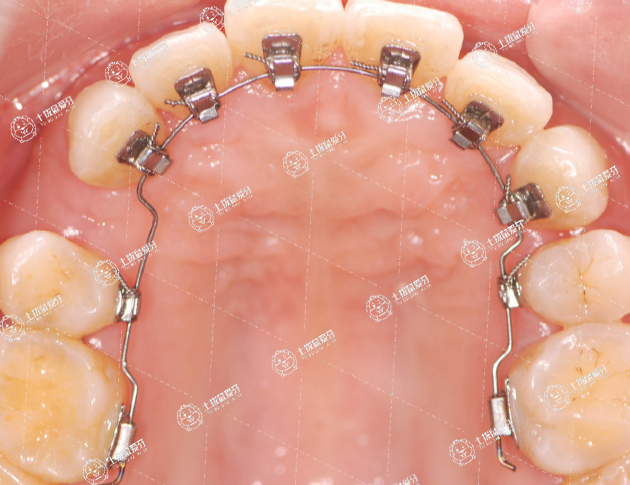

牙齒排列擁擠是臨床常見的錯頜畸形。輕度擁擠常表現(xiàn)為上下切牙扭轉(zhuǎn)錯位或尖牙輕度重向錯位,通常采用擴大牙弓的矯治方法進行治療,擁擠度只有2-4mm。

一、可用口外唇弓推磨牙向后,利用口外唇弓推上頜第一恒磨牙向后取得間隙,排齊前牙輕度的擁擠是臨床常見的矯治方法,此方法主要用于第二恒磨牙未萌出以前,特別適用于前移遠中的病例;

二、局部開展間隙是常用的擴大牙弓獲得間隙的局部開展矯正技術(shù)的矯治方法,主要用于個別牙齒擁擠錯位間隙不足,局部開展牙弓間隙來源主要靠前部牙弓弧度的增大;

三、可用細絲弓彎制各種曲來開展牙弓長度;

四、擴弓的矯治可分為分裂簧的慢速擴弓也可分為快速擴弓,取得間隙后更換其他可摘或固定矯治器排齊擁擠錯位的牙齒。中度和重度擁擠時牙列擁擠常達到4-8mm甚至8mm以上。采用減數(shù)的方法配合矯正器治療。拔牙矯治牙位的選擇通常是左右成對病牙優(yōu)先的原則